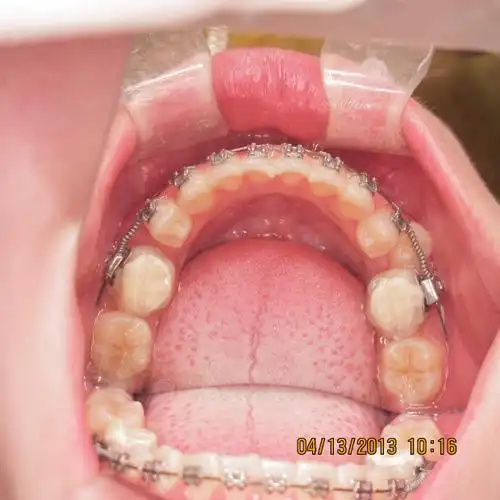

下颌阻生双尖牙矫治一例

图片尺寸620x620